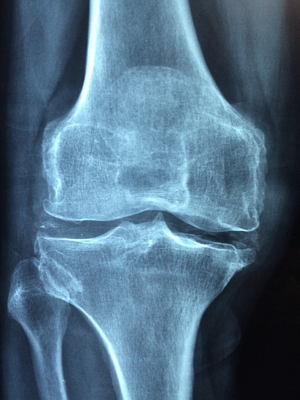

MSM 성분은 우리 몸의 연골을 생성하는 것에 도움을 주는 성분으로, 관련된 연구 자료에 따르면 관절염과 통증을 감소시킬 수 있다는 결과의 연구 자료가 많습니다.

근육통을 비롯한 여러 통증과 염증을 진정시켜줄 뿐만 아니라 무릎, 손목과 같은 부위의 퇴행성 관절염 증상을 완화하는 효과도 가지고 있습니다.

MSM은 관절 염증을 억제하는 항염 작용이 있습니다. 관절 염증을 감소시키고 관절과 관절 사이를 매끄럽게 해주는 관절액 생성을 증가시키는 데 도움을 준다고 합니다.